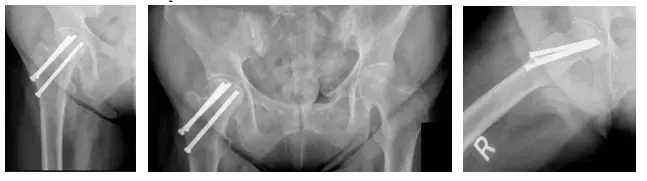

La paciente es una mujer de 68 años que acudió quejándose de dolor en la cadera derecha tras haber sido operada de una fractura anterior de cadera derecha. El paciente trajo radiografías para revisar, como se muestra a continuación, y se determinó que era el hardware de la cirugía anterior que estaba causando el dolor.

Las radiografías muestran la fijación de una fractura de cadera derecha con deformidad de la cabeza femoral